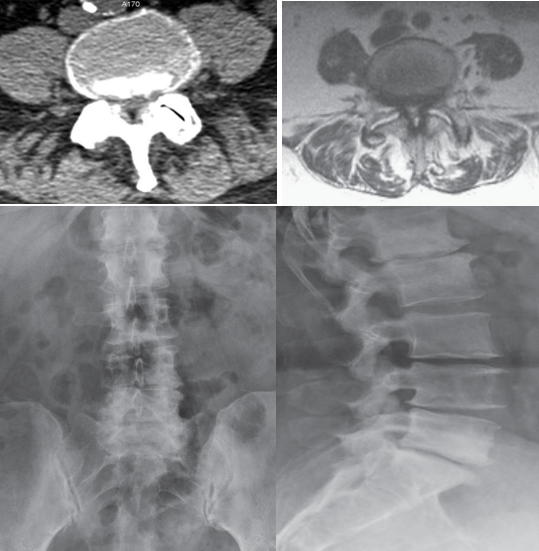

腰椎管狭窄症(1umbar spinal stenosis,LSS)是指各种原因引起的腰椎骨与软组织(关节突关节、椎板、黄韧带、椎间盘等)发生形态与组织结构的变化,导致中央椎管、神经根管、椎间孔处狭窄,使神经根和/或马尾神经受到压迫,引起一系列临床症状的疾病。常见的病因包括退变性、先天性、峡部裂滑脱、外伤性、医源性、代谢及内分泌疾病等。临床上以退变性腰椎管狭窄为主,多见于老年人。

关于手术治疗的研究很多,大多数研究显示手术治疗的近期及远期疗效优于保守治疗。椎板切除减压术和开窗减压术都是腰椎管狭窄可选择的术式。如果切除的骨质过多损害了脊柱的稳定,或者出现了峡部裂型或退行性腰椎滑脱,或者伴有后凸畸形时,那么就需要进行融合术。其他进行融合术的重要指征包括初次融合术后相邻节段的退变、减压术后出现复发性椎管狭窄或椎间盘突出。椎板切除术适用于有严重的、多节段椎管狭窄的老年患者,而开窗手术,包括保留后侧中央结构的双侧椎板切开术和部分的开窗手术,都是可供椎间盘完好的年轻患者选择的术式。